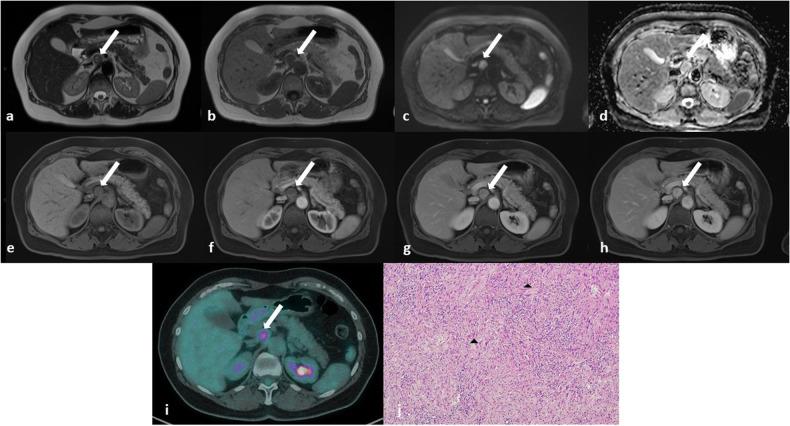

Benign nerve sheath tumors presenting as solitary retroperitoneal masses (RBNSTs) pose a complex diagnostic challenge for multidisciplinary teams regarding differential diagnosis, staging, and treatment planning. This article reviews the role played by different imaging techniques in assessing RBNSTs and elucidates their typical pathological features with a particular emphasis on the correlation between imaging and histological findings. Furthermore, some examples of retroperitoneal tumors that merit consideration in the process of differential diagnosis based on cross-sectional investigations (CSIs) are reported. The correlation between tissue architecture and appearance on imaging can help increase the accuracy of differential diagnosis with other retroperitoneal neoplasms at CSIs.

表现为孤立性腹膜后肿块的良性神经鞘瘤(RBNSTs)对多学科团队在鉴别诊断、分期和治疗规划方面构成了复杂的诊断挑战。本文回顾了不同成像技术在评估RBNSTs中所起的作用,并阐明了其典型的病理特征,特别强调了成像与组织学结果之间的相关性。此外,还报告了一些在基于横断面检查(CSI)进行鉴别诊断过程中值得考虑的腹膜后肿瘤实例。组织结构与成像表现之间的相关性有助于提高CSI时与其他腹膜后肿瘤鉴别诊断的准确性。